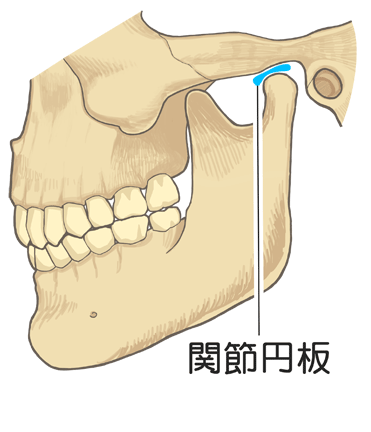

顎関節とは

顎関節とは、耳の少し前あたりにある頭蓋骨と下顎のつなぎ目のことを言います。

上顎は頭蓋骨にくっついていて動かすことはできないようになってます。

下顎は独立した骨になっていて、筋肉でぶら下がっているような形でくっついている状態です。

なので、下顎はいろんな方向に動かせますよね?

固定されている上顎と自由に動く下顎をつなげているのが顎関節と呼ばれるものになります。

その間に挟まれている軟骨を関節円板といいます。

この関節円板の動きが妨げられるとガクッと音が鳴ります。